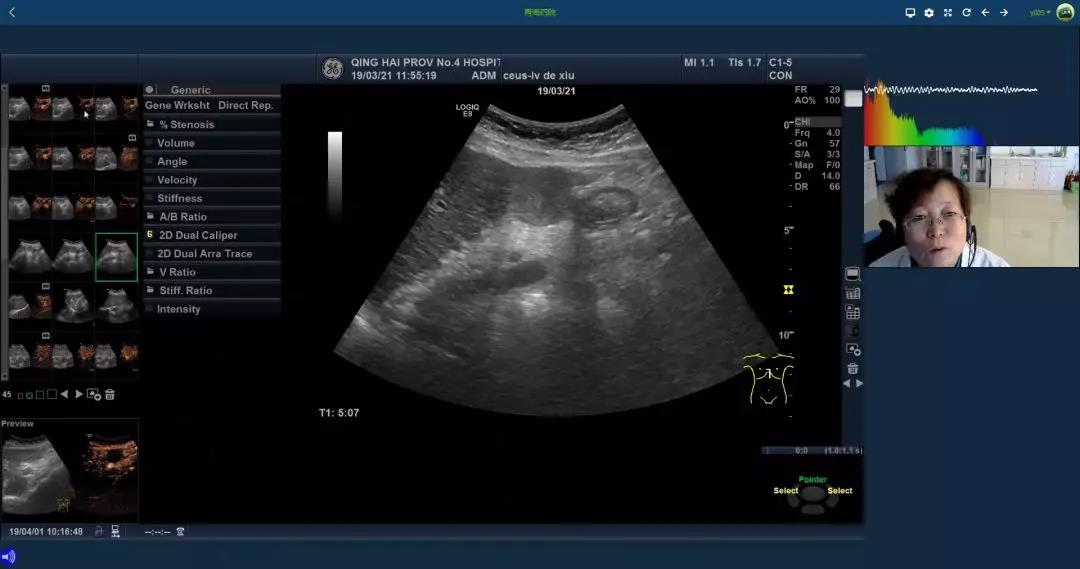

神经外科重症病房(NICU)床旁超声通过5G传输会诊

与其他静态影像技术不同,超声图像具有实时动态的特点,需要稳定、快速、低延迟的数据传输以保证会诊的实时性。受限于既往网络技术的局限性,超声影像数据传输的稳定性、实时性方面存在巨大挑战。5G技术的出现,带来了稳定、安全、快速的网络服务,显著强化上述大数据传输远程会诊系统的交互功能,极大提高了基层医疗机构的服务质量与就医体验,同时能缓解行业高水平医师不足的现状。

在本次5G超声实景观摩过程中,不仅实现了高清动态超声影像同步呈现,同时在后台为每一例患者完成了近2个G的原始医疗数据传输。在大数据医疗时代的今天,对于医疗数据的关注已达到前所未有的高度。以往,宝贵的医疗数据由于缺乏即刻传输的手段而被丢弃,一方面浪费了宝贵的数据资料,同时造成严肃的医疗活动无迹可寻。5G技术的出现,解决了基层患者超声影像资料的传输和保存问题,赋予了远程医疗全新的内涵。